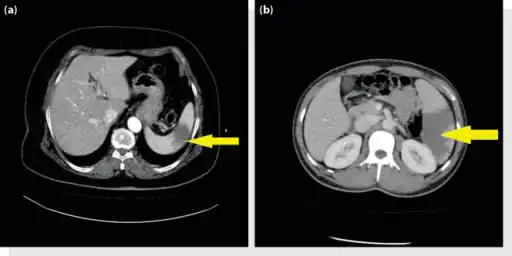

a, b) Splenic infarction. -

Splenic infarct seen on CT

An abdominal CT scan is the most commonly used modality to confirm the diagnosis,[3] although abdominal ultrasound can also contribute.[16][17][18]